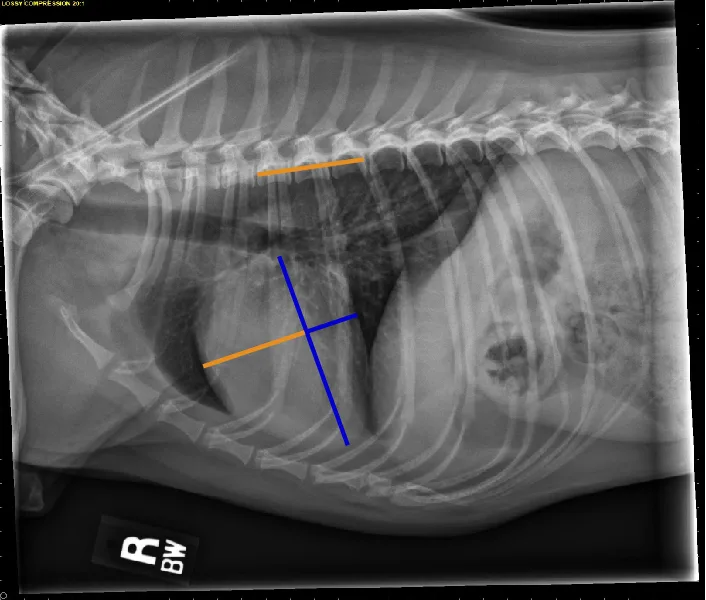

FIGURE 12 Representation of the VRHi with a value of 2.9 in a dog with a normal cardiac silhouette (left), and a dog with pulmonic stenosis and right-side heart enlargement with a VRHi value of 3.6 (right). Using the right lateral projection for measurement, a value ≥3.5 detects right-sided heart enlargement with a sensitivity of 68% and specificity of 86%.16 Images courtesy of Federico Villaplana Grosso, DACVR, DECVR, and Bruna Del Nero, DACVIM (Cardiology). Illustration courtesy of Jose Narvaez Perez